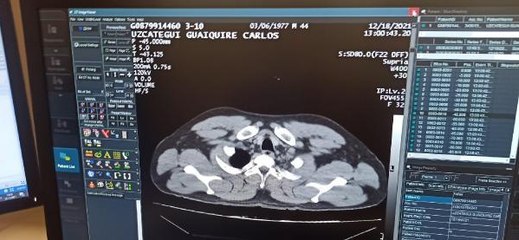

Venezuela'dan Türkiye'ye gelen C.M.U.G İstanbul Havalimanı'nda aniden rahatsızlanarak bayıldı. Yapılan kontrollerde şüphelinin midesi ve bağırsaklarında 12 adet kapsül şeklinde sarılı kokain tespit edildi.